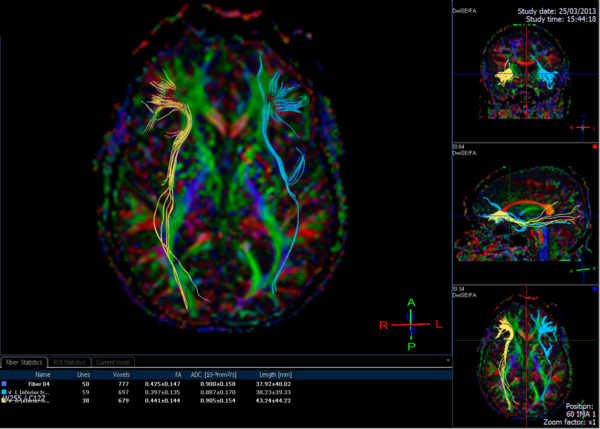

Réparer le cerveau… et après?

Traumatisme crânien, tumeur, accident vasculaire cérébral… quand le cerveau est atteint, tout l’être...